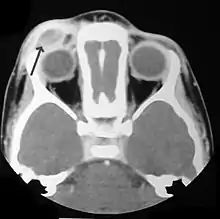

Imaging may be evident in chest X-rays with micronodular and reticular changes of the lungs with cyst formation in advanced cases. MRI and High-resolution CT may show small, cavitated nodules with thin-walled cysts. MRI scan of the brain can show three groups of lesions such as tumourous/granulomatous lesions, nontumourous/granulomatous lesions, and atrophy. Tumourous lesions are usually found in the hypothalamic-pituitary axis with space-occupying lesions with or without calcifications. In non-tumourous lesions, there is a symmetrical hyperintense T2 signal with hypointense or hyperintense T1 signal extending from grey matter into the white matter. In the basal ganglia, MRI shows a hyperintense T1 signal in the globus pallidus.[28]